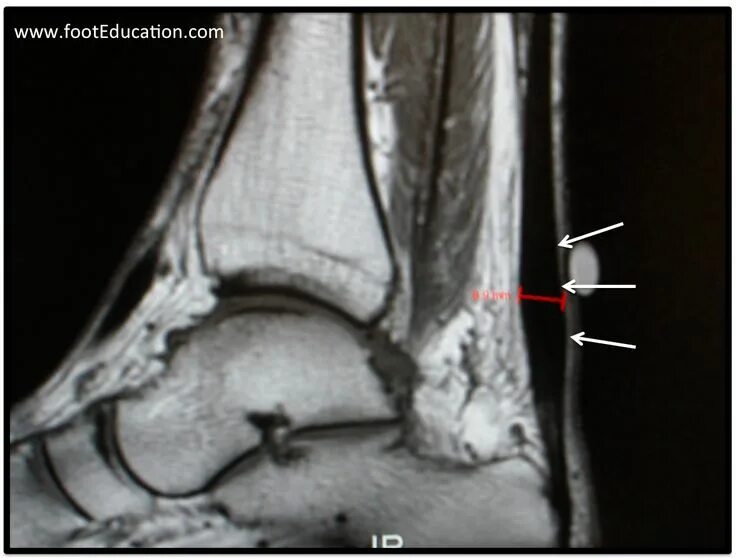

Мрт ахиллового сухожилия